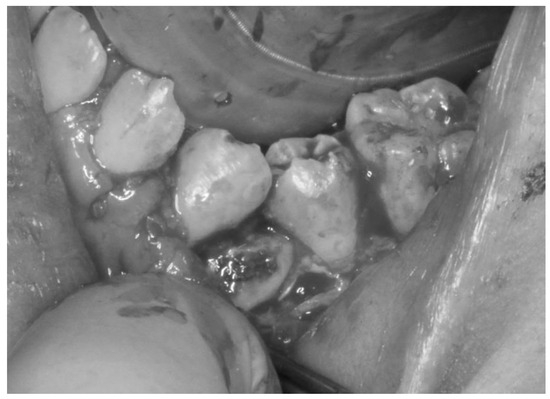

The treatment was carried out under general anesthesia with the aim of improving his oral hygiene. Initial observation of his oral condition was carefully completed. Dental X-ray and intraoral images during the administration of analgesic were obtained before starting the surgery (Figure 2 and Figure 3). A local anesthetic, proparacaine hydrochloride/felypressin (Citanest-Octapressin Cartridge for Dental use®), was injected into the affected area. An incision was made around the area along the cervical region and the oral mucosa was removed, which revealed the concealed tooth. It was observed from the left buccal side, but it was considered to be partially ankylosed. Then, a part of the target tooth was histopathologically examined to determine if there was any sign of ankylosis around it. Eventually, the tooth was divided into parts for smooth extraction, and the incision was closed using absorbable sutures (Figure 4).

Figure 2. Dental X-ray image of the left mandibular region of the patient’s mouth, taken under general anesthesia. This revealed hard tissue between the first and second mandibular premolars, which was similar in shape to part of a tooth crown.